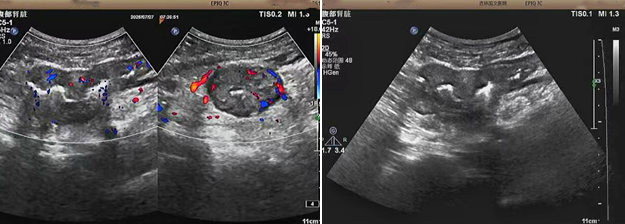

超聲檢查的結(jié)果進(jìn)一步揭示了病情的細(xì)節(jié):下腹部偏左腸壁顯著增厚,原本清晰的層次結(jié)構(gòu)遭到破壞,周圍脂肪間隙變得模糊,網(wǎng)膜回聲也出現(xiàn)增強的現(xiàn)象;同時,腸腔狹窄的情況也得到了確認(rèn)。經(jīng)過完善的檢查,最終將病變精準(zhǔn)定位在乙狀結(jié)腸 - 直腸交界區(qū),并且對病變范圍及周圍浸潤情況做出了評估,這些關(guān)鍵信息為后續(xù)的診療工作提供了重要依據(jù),讓醫(yī)生們能更有針對性地制定治療方案。

我院超聲檢查在此次診療過程中展現(xiàn)出了顯著的技術(shù)亮點。一方面,它能做到 “明察秋毫”,通過高頻探頭可以清晰地顯示腸壁各層結(jié)構(gòu)的變化,為臨床判斷病變性質(zhì)提供了客觀、準(zhǔn)確的依據(jù),讓醫(yī)生能更清晰地了解腸道內(nèi)部的病變狀態(tài),另一方面,它實現(xiàn)了 “精準(zhǔn)評估”,不僅準(zhǔn)確找到了病變的位置,還能全面評估病變對周圍組織的影響,這對于協(xié)助醫(yī)生制定科學(xué)合理的治療方案起到了至關(guān)重要的作用,有助于提高治療的有效性和安全性。